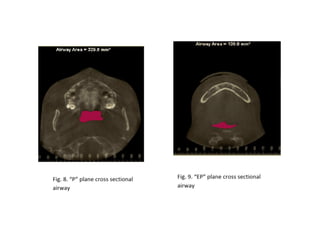

RME

• Maxillary constriction in particular has been

postulated to play a role in the pathophysiology

of OSA because of its association with low tongue

posture that may contribute to the orophayrnx

airway narrowing (Subtelny 1954).

• Pirelli et al. grouped 31 children with OSA and

followed them up to 4 months after RME

treatment. All of these children had their apnea-

hypoapnea index decreased while their mean

maxillary cross sectional width expanded to

about 4.5mm.